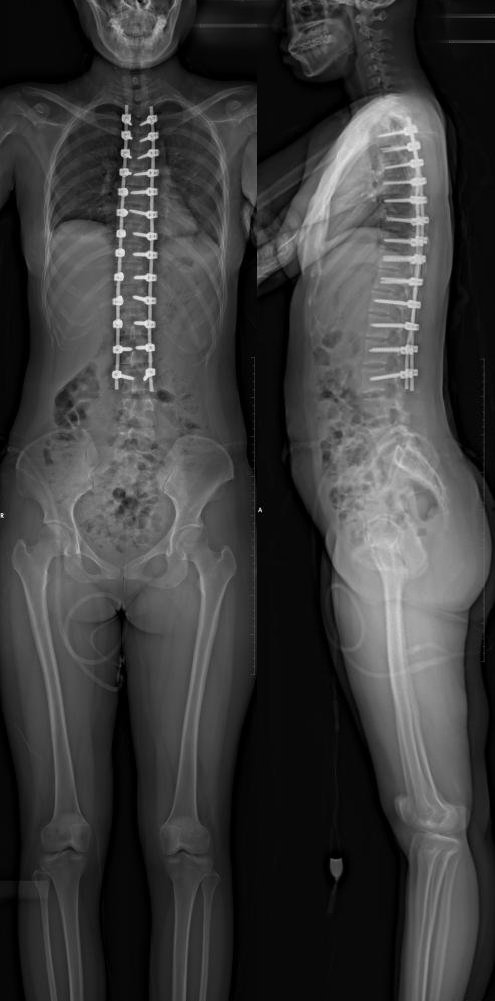

术后影像资料

术后检查影像

德康医疗脊柱畸形方案

LEO胸腰后路钉棒系统功能强大,配件齐全。系统内包含矫形用单平面螺钉、VSS惟德脊柱矫形工具、各类骨钩及多米诺连接器,助力脊柱畸形轻松矫正。